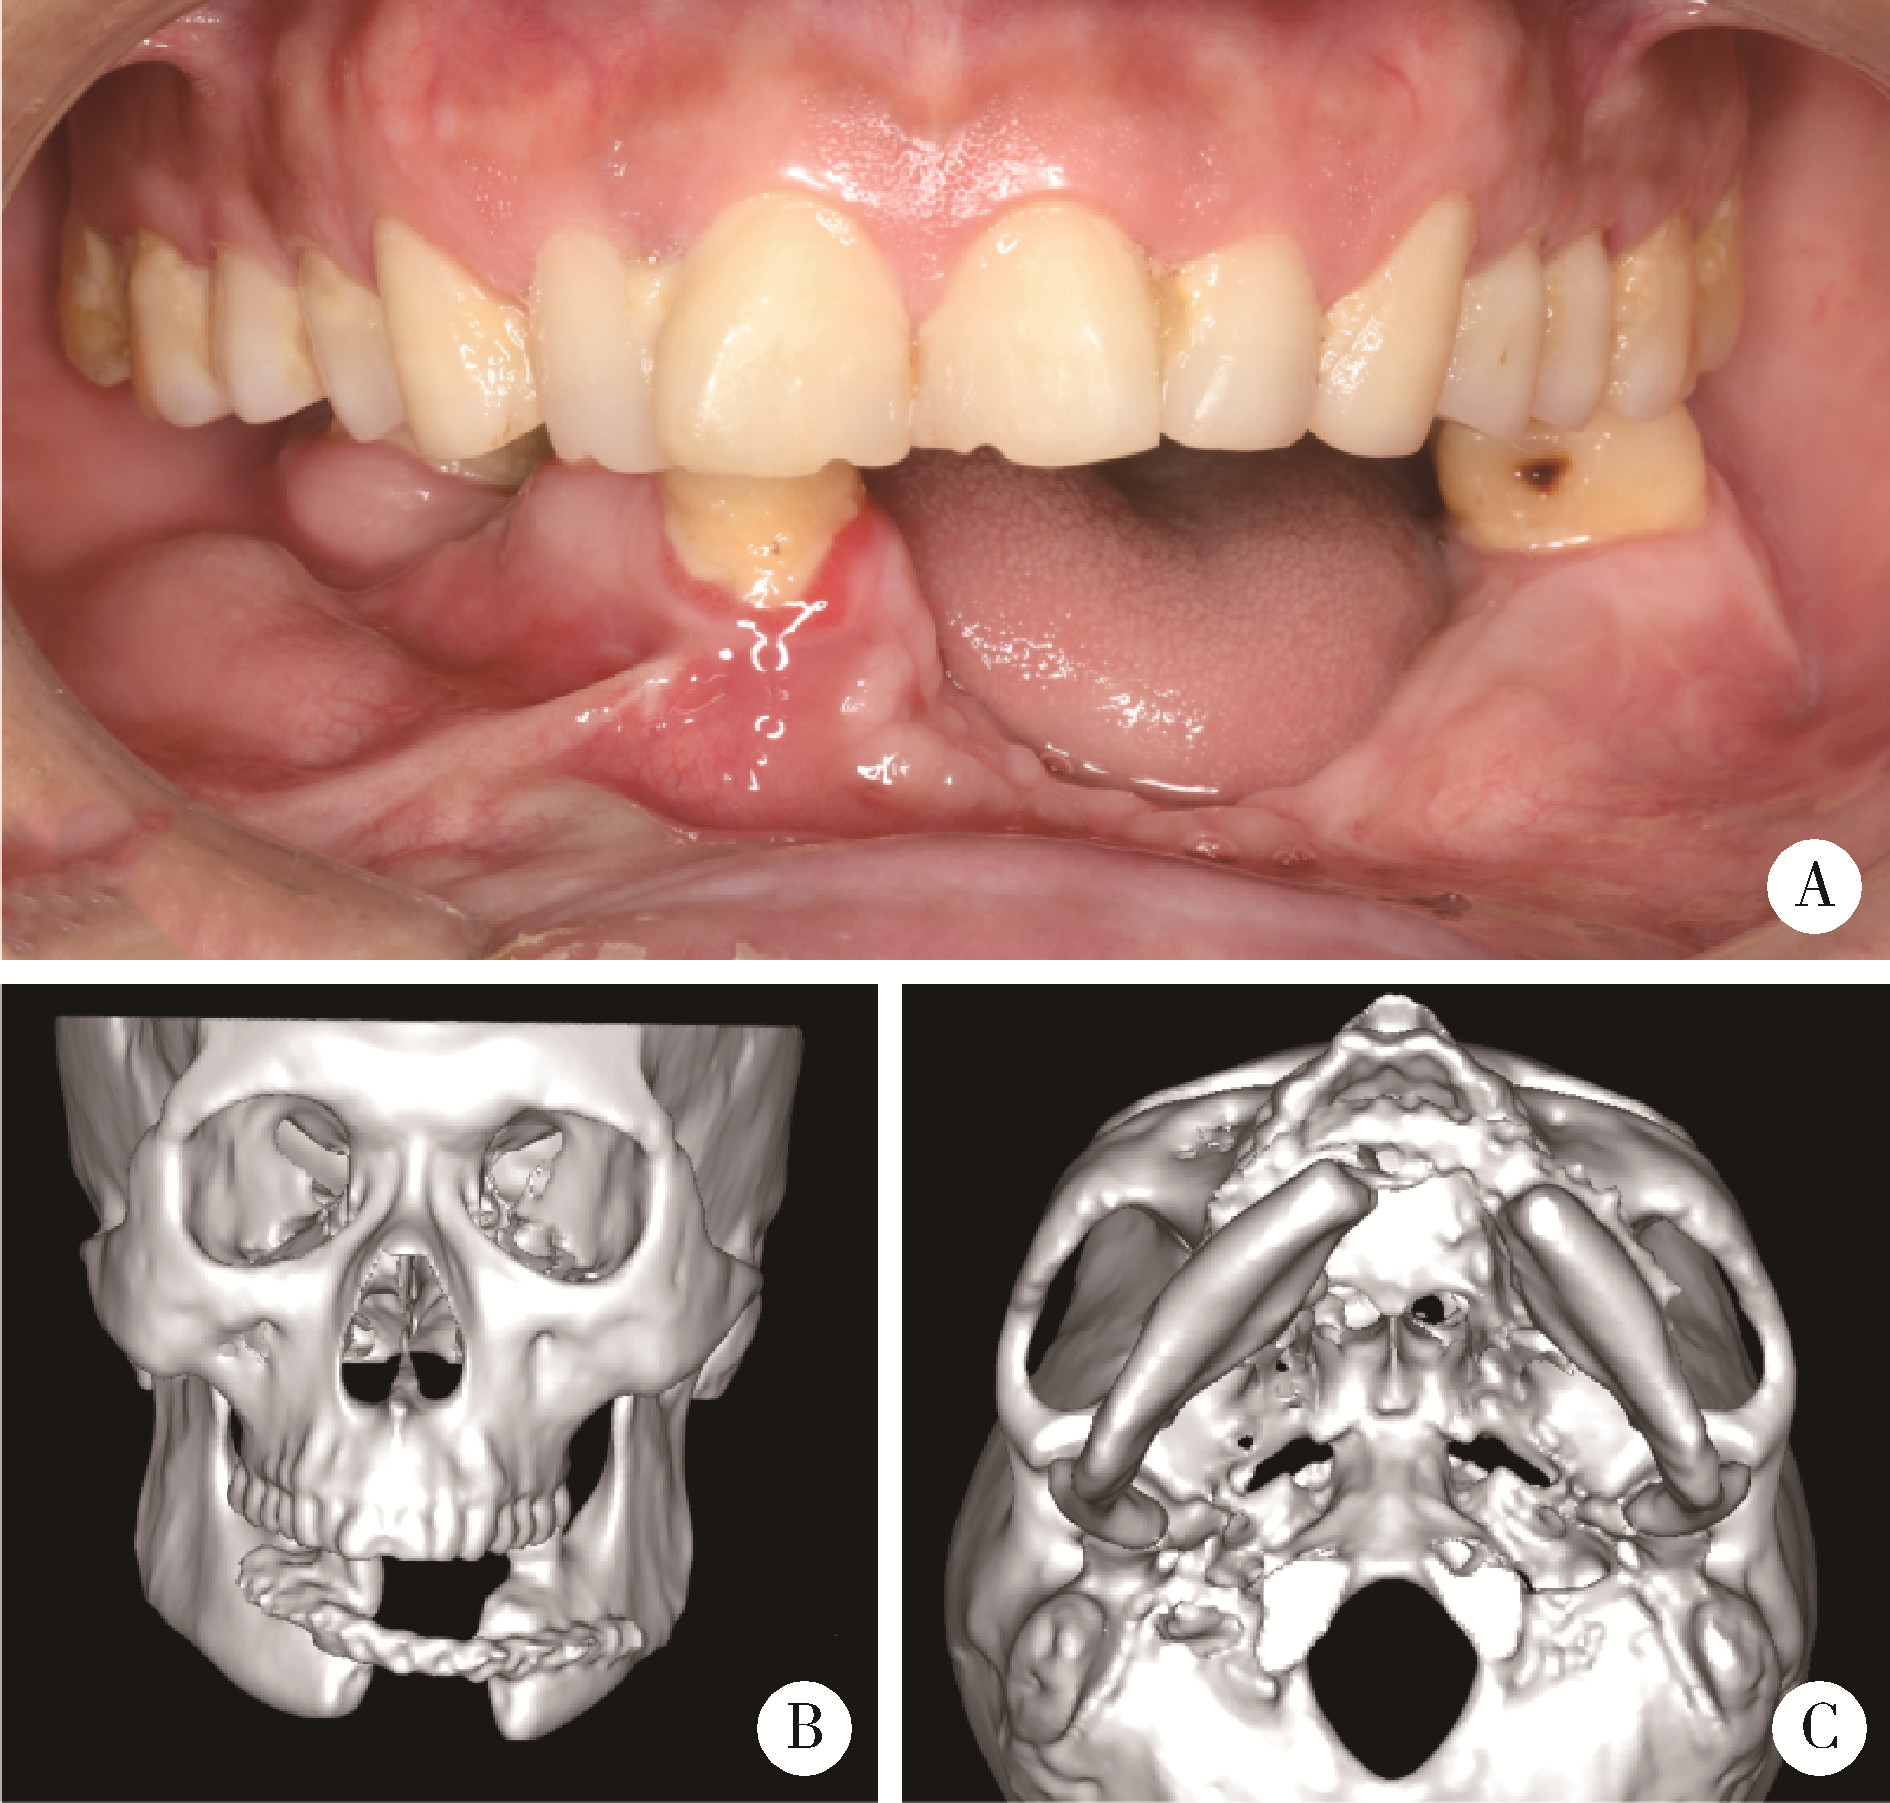

图3

病例4影像资料"

5例患者的信息"

Case No. Gender Age Diagnosis Defect type (according to Jewer classification) Defect area (using FDI system for teeth)

1 Female 46 Fibromyxoma LC 37-41

2 Female 55 Ameloblastoma LCL 33-47

3 Male 25 Ossifying fibroma LC 31-right mandibular angle

4 Male 43 Mandibular defect secondary to resection for ameloblastoma 6 months ago LCL 35-43

5 Male 27 Mandibular defect secondary to resection for keratocyst 2 years ago L 47-right mandibular angle